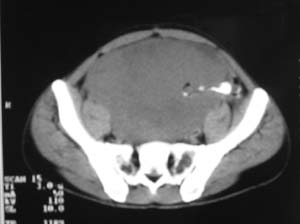

以下是引用zjzjr在2007-9-27 22:20:00的发言:[br]肠腔受推移,未见明显扩张及液平,所以考虑是肠外病灶, 间叶源性肿瘤?脂肪瘤?建议增强。

以下是引用guzhongliangddd在2007-9-27 23:21:00的发言:[br][br]与肠内高密度相同,病灶应该没有钙化,我认为首先考虑是间叶组织的良性肿瘤。建议楼主做后重建观察。中线区域大血管旁未见确切增大淋巴结。病灶对肠道只是推移关系。

以下是引用余辉在2007-9-27 22:24:00的发言:[br]暂考虑肠道间质来源肿瘤如小肠平滑肌肉瘤/瘤可能,应该增强